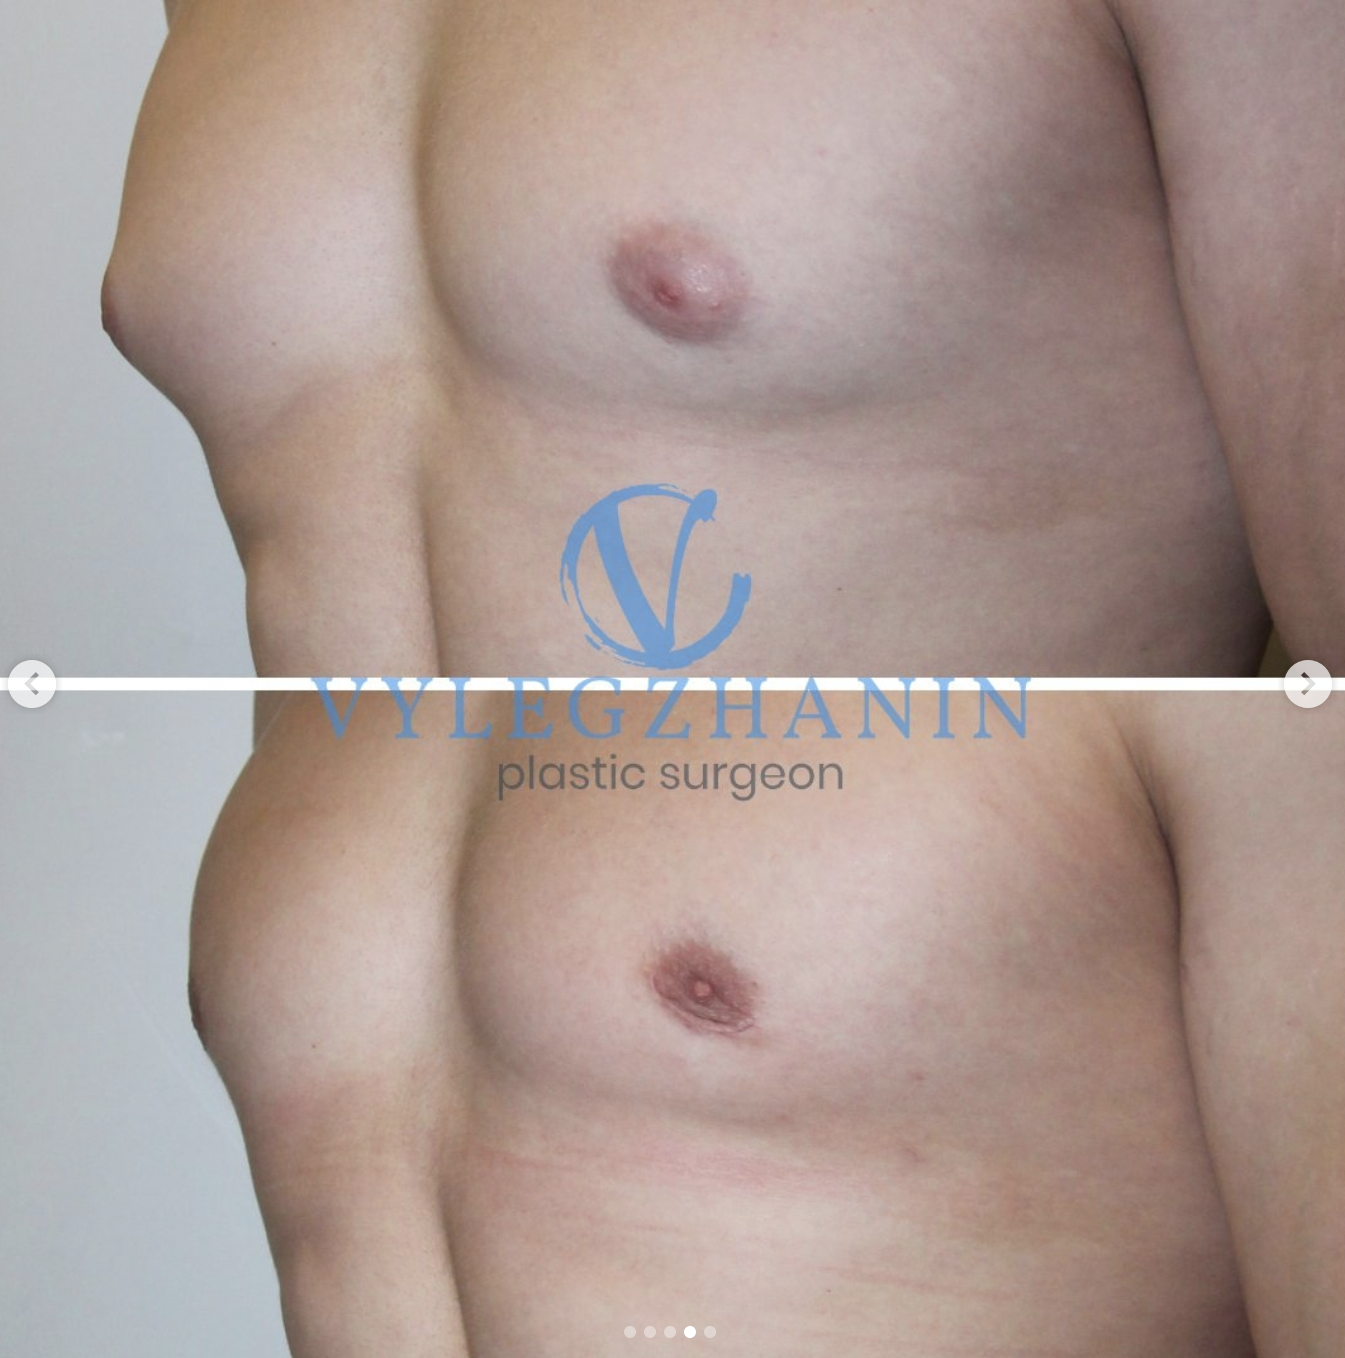

Аномалии молочной железы: медицинские примеры и визуализация